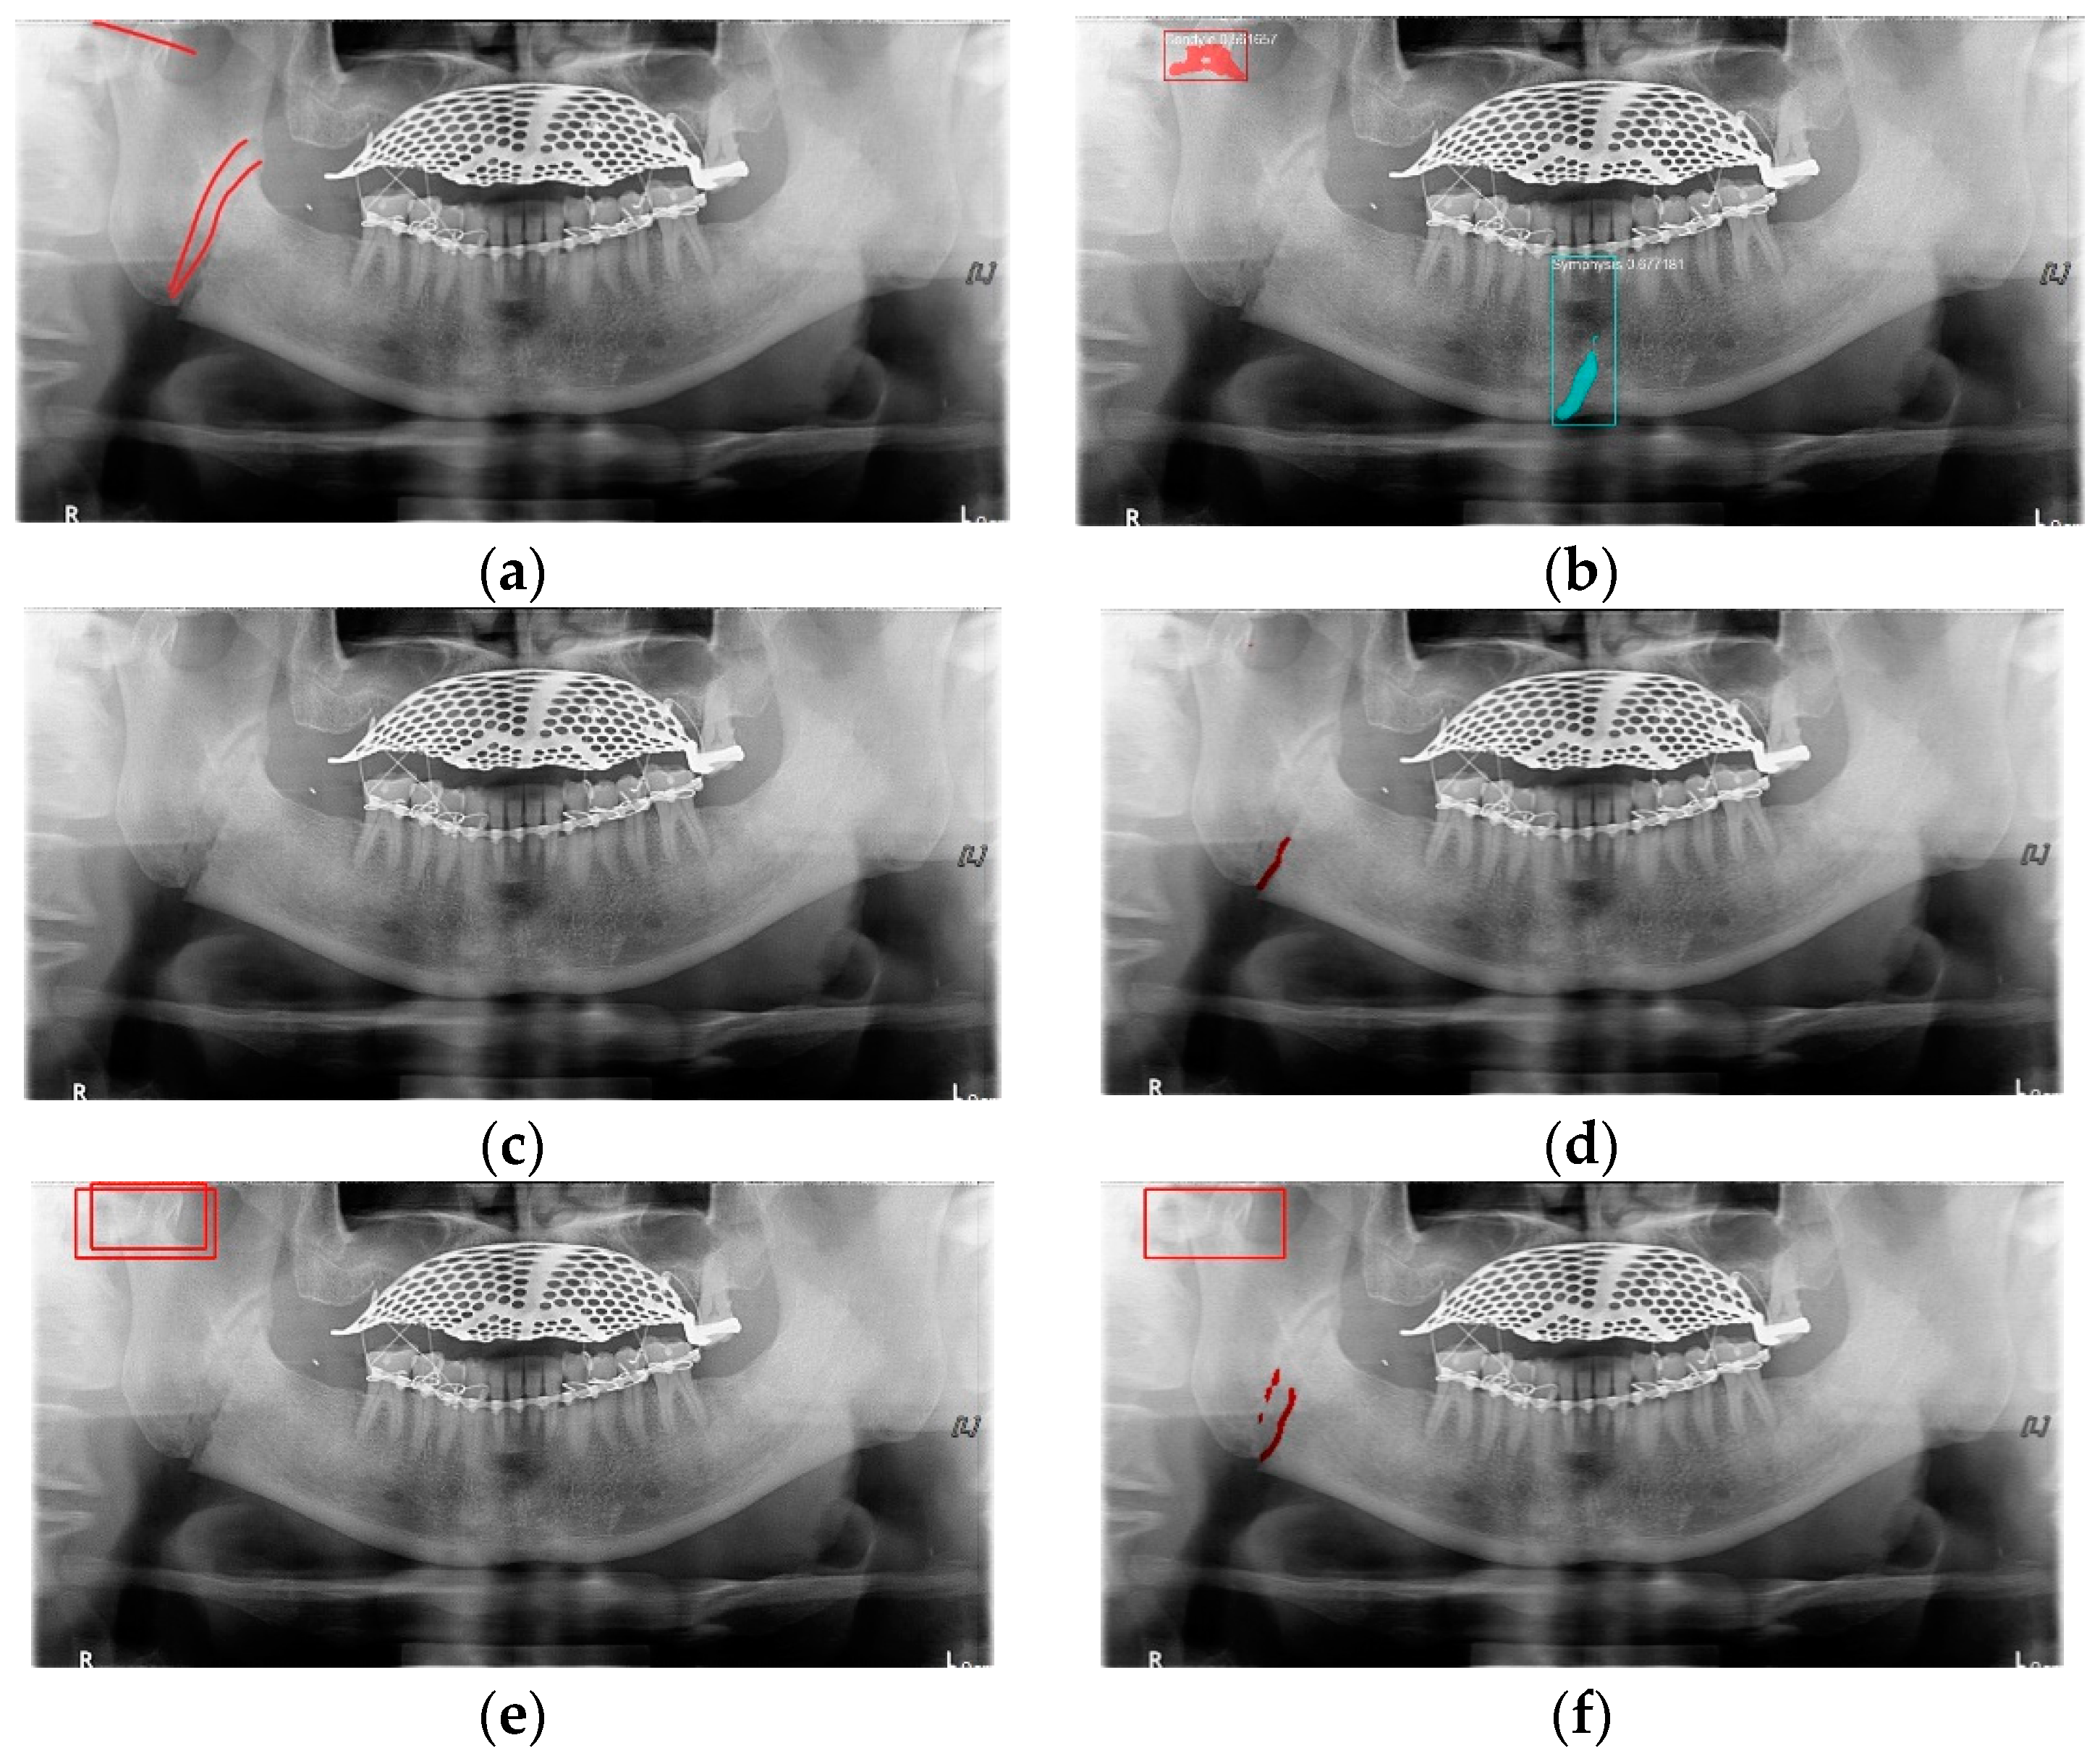

In Table 6, the parameters used for training are indicated, and in Figure 11, Figure 12 and Figure 13, the results of the doctor’s diagnosis, Mask R-CNN, YOLOv4, U-Net, LAT YOLOv4, and U-Net withYOLOv4 are compared. Figure 11 illustrates fractures in the angle and condylar regions, and in Mask R-CNN, the symphysis is misdiagnosed as a fracture. In Figure 12, the Mask R-CNN misdiagnoses the symphysis as a fracture, the result of the fact that the YOLOv4 module has better performance detecting angle fractures rather than does the LAT YOLOv4, as shown in Figure 12c,e. In short, the LAT-processed image does not always have the advantage of better revealing fractures compared with the normal panoramic radiograph.

Figure 11.

The comparison of mandibular fracture detection: (a) oral and maxillofacial radiologist, (b) Mask R-CNN (with colored polygons and boxes), (c) YOLOv4, (d) U-Net (with a red line), (e) LAT YOLOv4 (with red boxes), and (f) U-Net with LAT YOLOv4 (with a red box and lines).